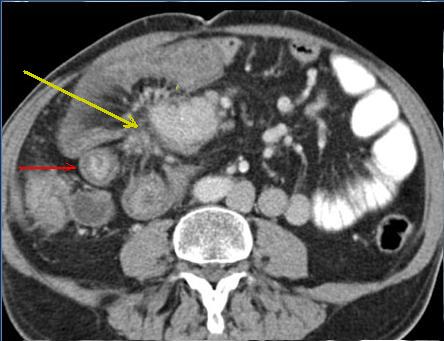

| Adeno carcinoma duodenum :

Epaissisement de la paroie duodenum en

circonferentielle , infiltrant et irreguliairement .

Image de stenose de la lumiere du portion lesionaire

. Image TDM en coupe axilae . |

Mema cas ( fleche

rouge ) en coupe cornale ( frontal )